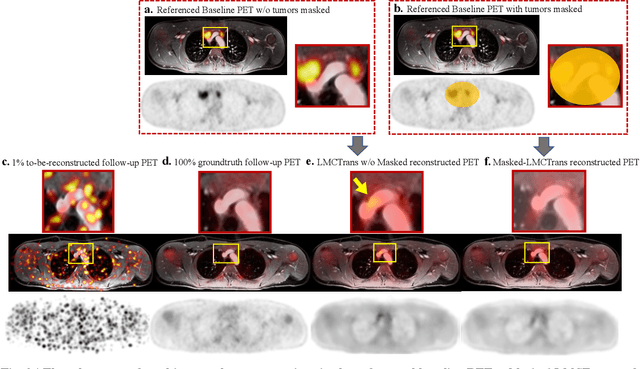

Abstract:Despite its tremendous value for the diagnosis, treatment monitoring and surveillance of children with cancer, whole body staging with positron emission tomography (PET) is time consuming and associated with considerable radiation exposure. 100x (1% of the standard clinical dosage) ultra-low-dose/ultra-fast whole-body PET reconstruction has the potential for cancer imaging with unprecedented speed and improved safety, but it cannot be achieved by the naive use of machine learning techniques. In this study, we utilize the global similarity between baseline and follow-up PET and magnetic resonance (MR) images to develop Masked-LMCTrans, a longitudinal multi-modality co-attentional CNN-Transformer that provides interaction and joint reasoning between serial PET/MRs of the same patient. We mask the tumor area in the referenced baseline PET and reconstruct the follow-up PET scans. In this manner, Masked-LMCTrans reconstructs 100x almost-zero radio-exposure whole-body PET that was not possible before. The technique also opens a new pathway for longitudinal radiology imaging reconstruction, a significantly under-explored area to date. Our model was trained and tested with Stanford PET/MRI scans of pediatric lymphoma patients and evaluated externally on PET/MRI images from T\"ubingen University. The high image quality of the reconstructed 100x whole-body PET images resulting from the application of Masked-LMCTrans will substantially advance the development of safer imaging approaches and shorter exam-durations for pediatric patients, as well as expand the possibilities for frequent longitudinal monitoring of these patients by PET.